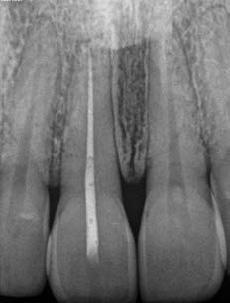

1. a–f ábrák: A cingulumon keresztül gömbfúróval kialakított hozzáférés a trepanációs kavitás labiális irányba történő túlzott mértékű kiterjesztését eredményezheti, és ez lényegesen növelheti a perforáció esélyét (a). A guttapercha átsejlik a lágyrészek alatt (b). Klinikailag igazolt perforáció (c). A preoperatív sagittális irányú CBCT-szeleten jól látható a labiális perforáció (d). Labiális irányú perforáció (fekete nyíl; e). A tényleges gyökércsatorna (piros nyíl; f).

A frontfogakban történő hozzáférési nyílás kialakítása

A frontfogakban a hozzáférési nyílás kialakítását hagyományosan a fogak linguális vagy palatinális felszínén, a cingulumon keresztül egy gömbfúró segítségével kezdjük. A linguálisan elhelyezkedő kiemelkedés teljes eltávolítása, továbbá a pulpaszarvak teljes feltárása egy háromszög alakú hozzáférési nyílást eredményez. 7 Ezt a módszert a fogak esztétikai megjelenésének megőrzése érdekében fejlesztették ki. Ez azonban időnként a saját foganyag indokolatlan eltávolításával, a trepanációs kavitás labiális irányba történő túlzott kiterjesztésével, perforációval, valamint a fog kritikus helyen, a pericervikális dentin (PCD) területén történő meggyengítésével jár (1. a–f és 2. a-b ábrák). 19 Felmerült, hogy a pericervikális dentin rendkívül fontos szerepet játszik a rágóerő gyökerek irányába történő továbbításában, és elképzelhető, hogy a gyökérkezelt fogak hosszú távú megtartása szempontjából a legfontosabb tényező az ép pericervikális dentin megőrzése lehet. 20 A cingulumon keresztül történő hozzáférési nyílás

5. a–l. ábrák: Az incisális élen keresztül kialakított hozzáférés lehetővé teszi a pericervikális dentin megőrzését. Kalcifikáció esetén CBCT-felvétel készítése hasznosnak bizonyulhat a hozzáférési nyílás tervezése során (a–d) . Minden fog koronai helyreállítása a gyökértömés elkészítésével egyidejűleg történt. A négyéves (e–h) és a kétéves (i–l) kontrollok alkalmával készített röntgenfelvételeken teljes gyógyulás látható. Mindkét fog tünetmentes és funkcióképes volt. (Dr. Viraj Vora esetei)

kialakítása során fennáll a fog labiális irányú perforációjának veszélye, mivel ilyenkor a foganyag elvételét labiális irányú fúrótartással kezdjük. Nemrégiben újragondolták a